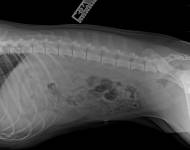

MVDr. Meloun: Lumbosakrální přechodový obratel